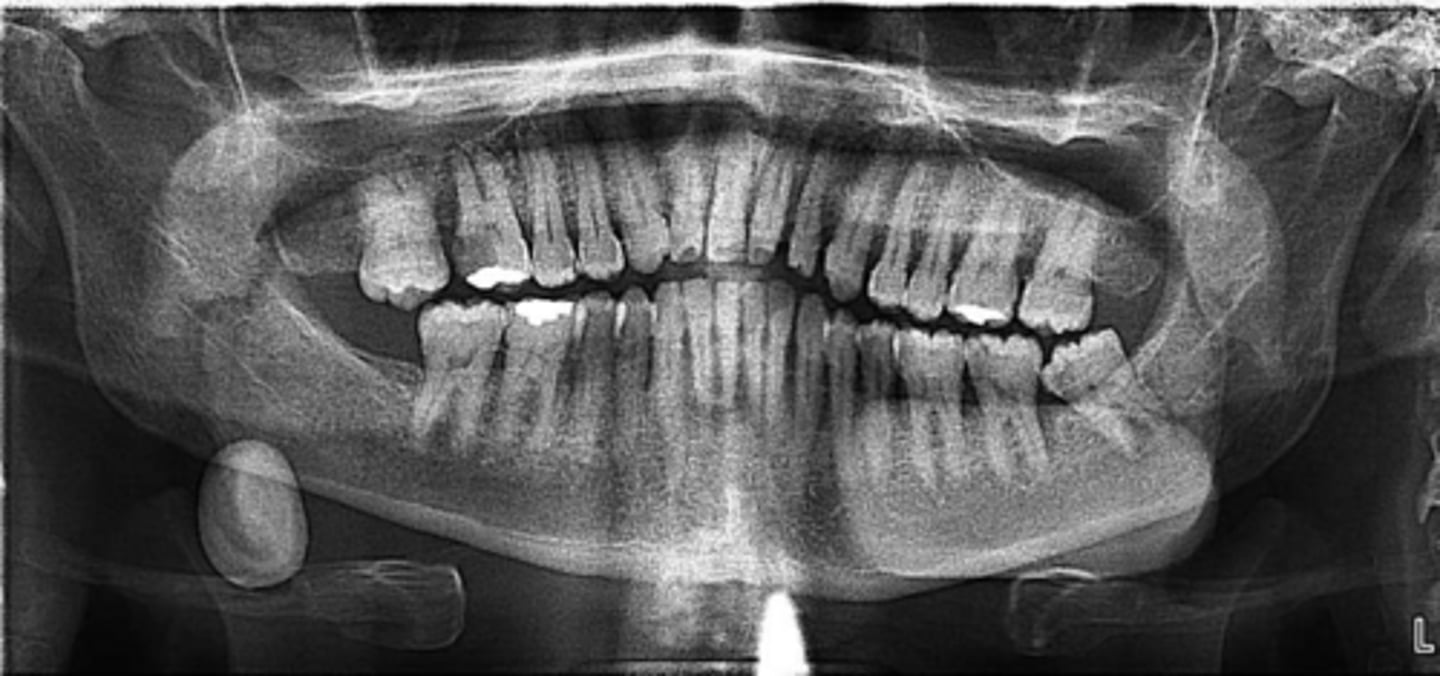

ID the pathology:

Swelling in wharton's duct

Sialolithiasis

ID the pathology during surgery:

Associated with pain upon salivation

What pathology is associated with pain upon salivation?

submandibular gland

80% of Sialolithiasis are associated with what gland?

Radiopaque mass

What is the radiographic features of a

Sialolithiasis?

ID the pathology based on the histology findings:

- Laminated calcified structure with central nidus

- Milking stone toward duct orifice